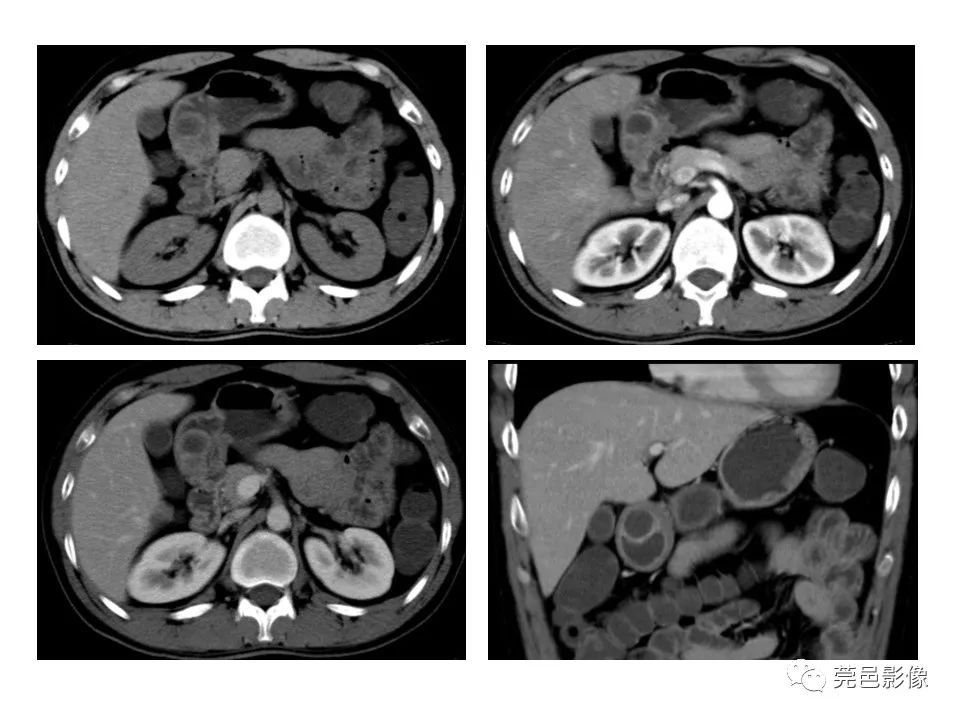

典型表现:“内衬黏膜,外绕平滑肌”;胃壁五层结构内的低回声或无回声病

灶,多位于粘膜下层,与正常胃壁共有平滑肌层或浆膜层;内衬黏膜产生特征性的高回声,相邻的外绕平滑肌层则为低回声,从而构成胃重复囊壁的“双层征” (50%);有时超声下可见重复畸形囊壁的蠕动收缩改变(良好的平滑肌),该征象有助于同肠系膜囊肿、卵巢囊肿等腹腔囊性肿块鉴别;少数与胃腔相通的管状重复畸形,EUS下可见其收缩蠕动,是胃重复畸形的佐证